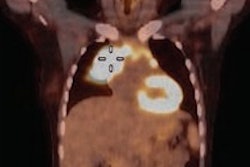

Patient undergoing PET/CT at the network's diagnostic center in Ufa."During the last decade this situation improved to some degree but at the national level, demand for PET/CT has not been satisfied," Sinitsyn noted. "Our hospital has an increasing flow of oncological patients and access to PET/CT is very important for management and treatment of many cancers cases."